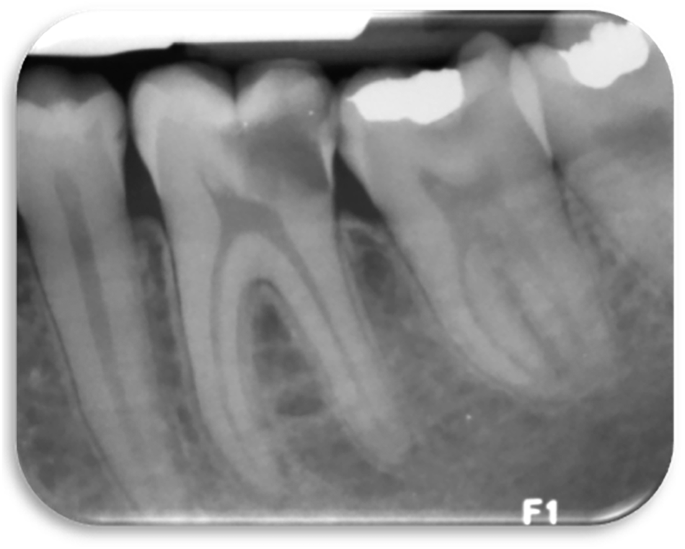

‘A 20-year-old female presents to your practice as an emergency appointment with shooting pain on eating and drinking from lower left quadrant. She is not able to specify a tooth. The pain lasts for an hour and is not relieved by analgesics.

Your oral examination reveals a carious lower left first molar, there are no sinuses or signs of swelling. The tooth is not tender to percussion. Cold testing revealed exaggerated response compared to the second molar, but the pain went away within 30-60 seconds. You take a radiograph which shows caries reaching the pulp and no apical radiolucency (Fig. 1). The pulpal diagnosis is an irreversible pulpitis and normal apical tissues in the lower left first molar.’